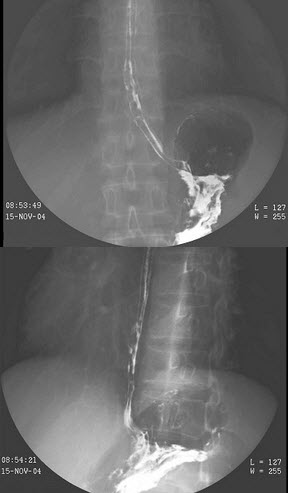

24、单项选择题

男,40岁,腹胀痛1月余。体检:脾肋下5cm,结合图像,最可能的诊断为()

A.正常食管

B.食管静脉曲张

C.食管胃底静脉曲张

D.贲门失弛缓

E.食管癌